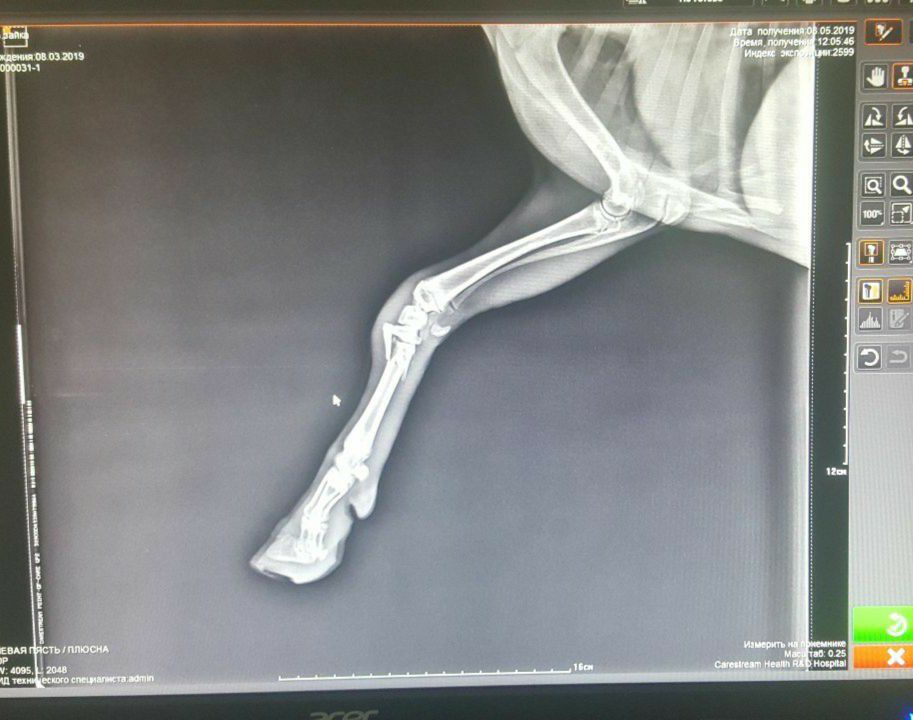

Цифровой рентген

Цифровой рентген кота или собаки с большой долей достоверности и информативности показывает состояние здоровья костей, суставов, легких, сердца, желудочно-кишечного тракта. Рентгенограмма передает структурные особенности исследуемых органов. Рентген позволяет диагностировать различные патологии. Ветеринарные специалисты назначают рентген кошек и собак для оценки состояния здоровья костной и мышечной системы, в частности, при переломе костей, дисплазии тазобедренного сустава, артрите у кошек или собак. Рентгенография также используется для исследования внутренних органов, включая сердце, легкие, печень, почки, кишечник, желудок. Позволяет обнаружить инородное тело, находящегося в желудке или кишечнике, а также наличия жидкости, опухоли.

Рентген для собак и кошек часто используются в сочетании с ультразвуком для более детальной диагностики состояния здоровья домашних животных. Рентгенография животных назначается:

Если животное травмировалось, рентген костно-суставной системы позволит оценить степень тяжести повреждений (перелом, трещина), а также детально рассмотреть участок повреждения, увидеть осколки, если травма тяжелая. Для врача это важные и необходимые сведения, позволяющие назначить оптимальную схему лечения. Рентген лап собаки или кошки позволяет правильно и своевременно спланировать лечение, цена его при этом невелика.